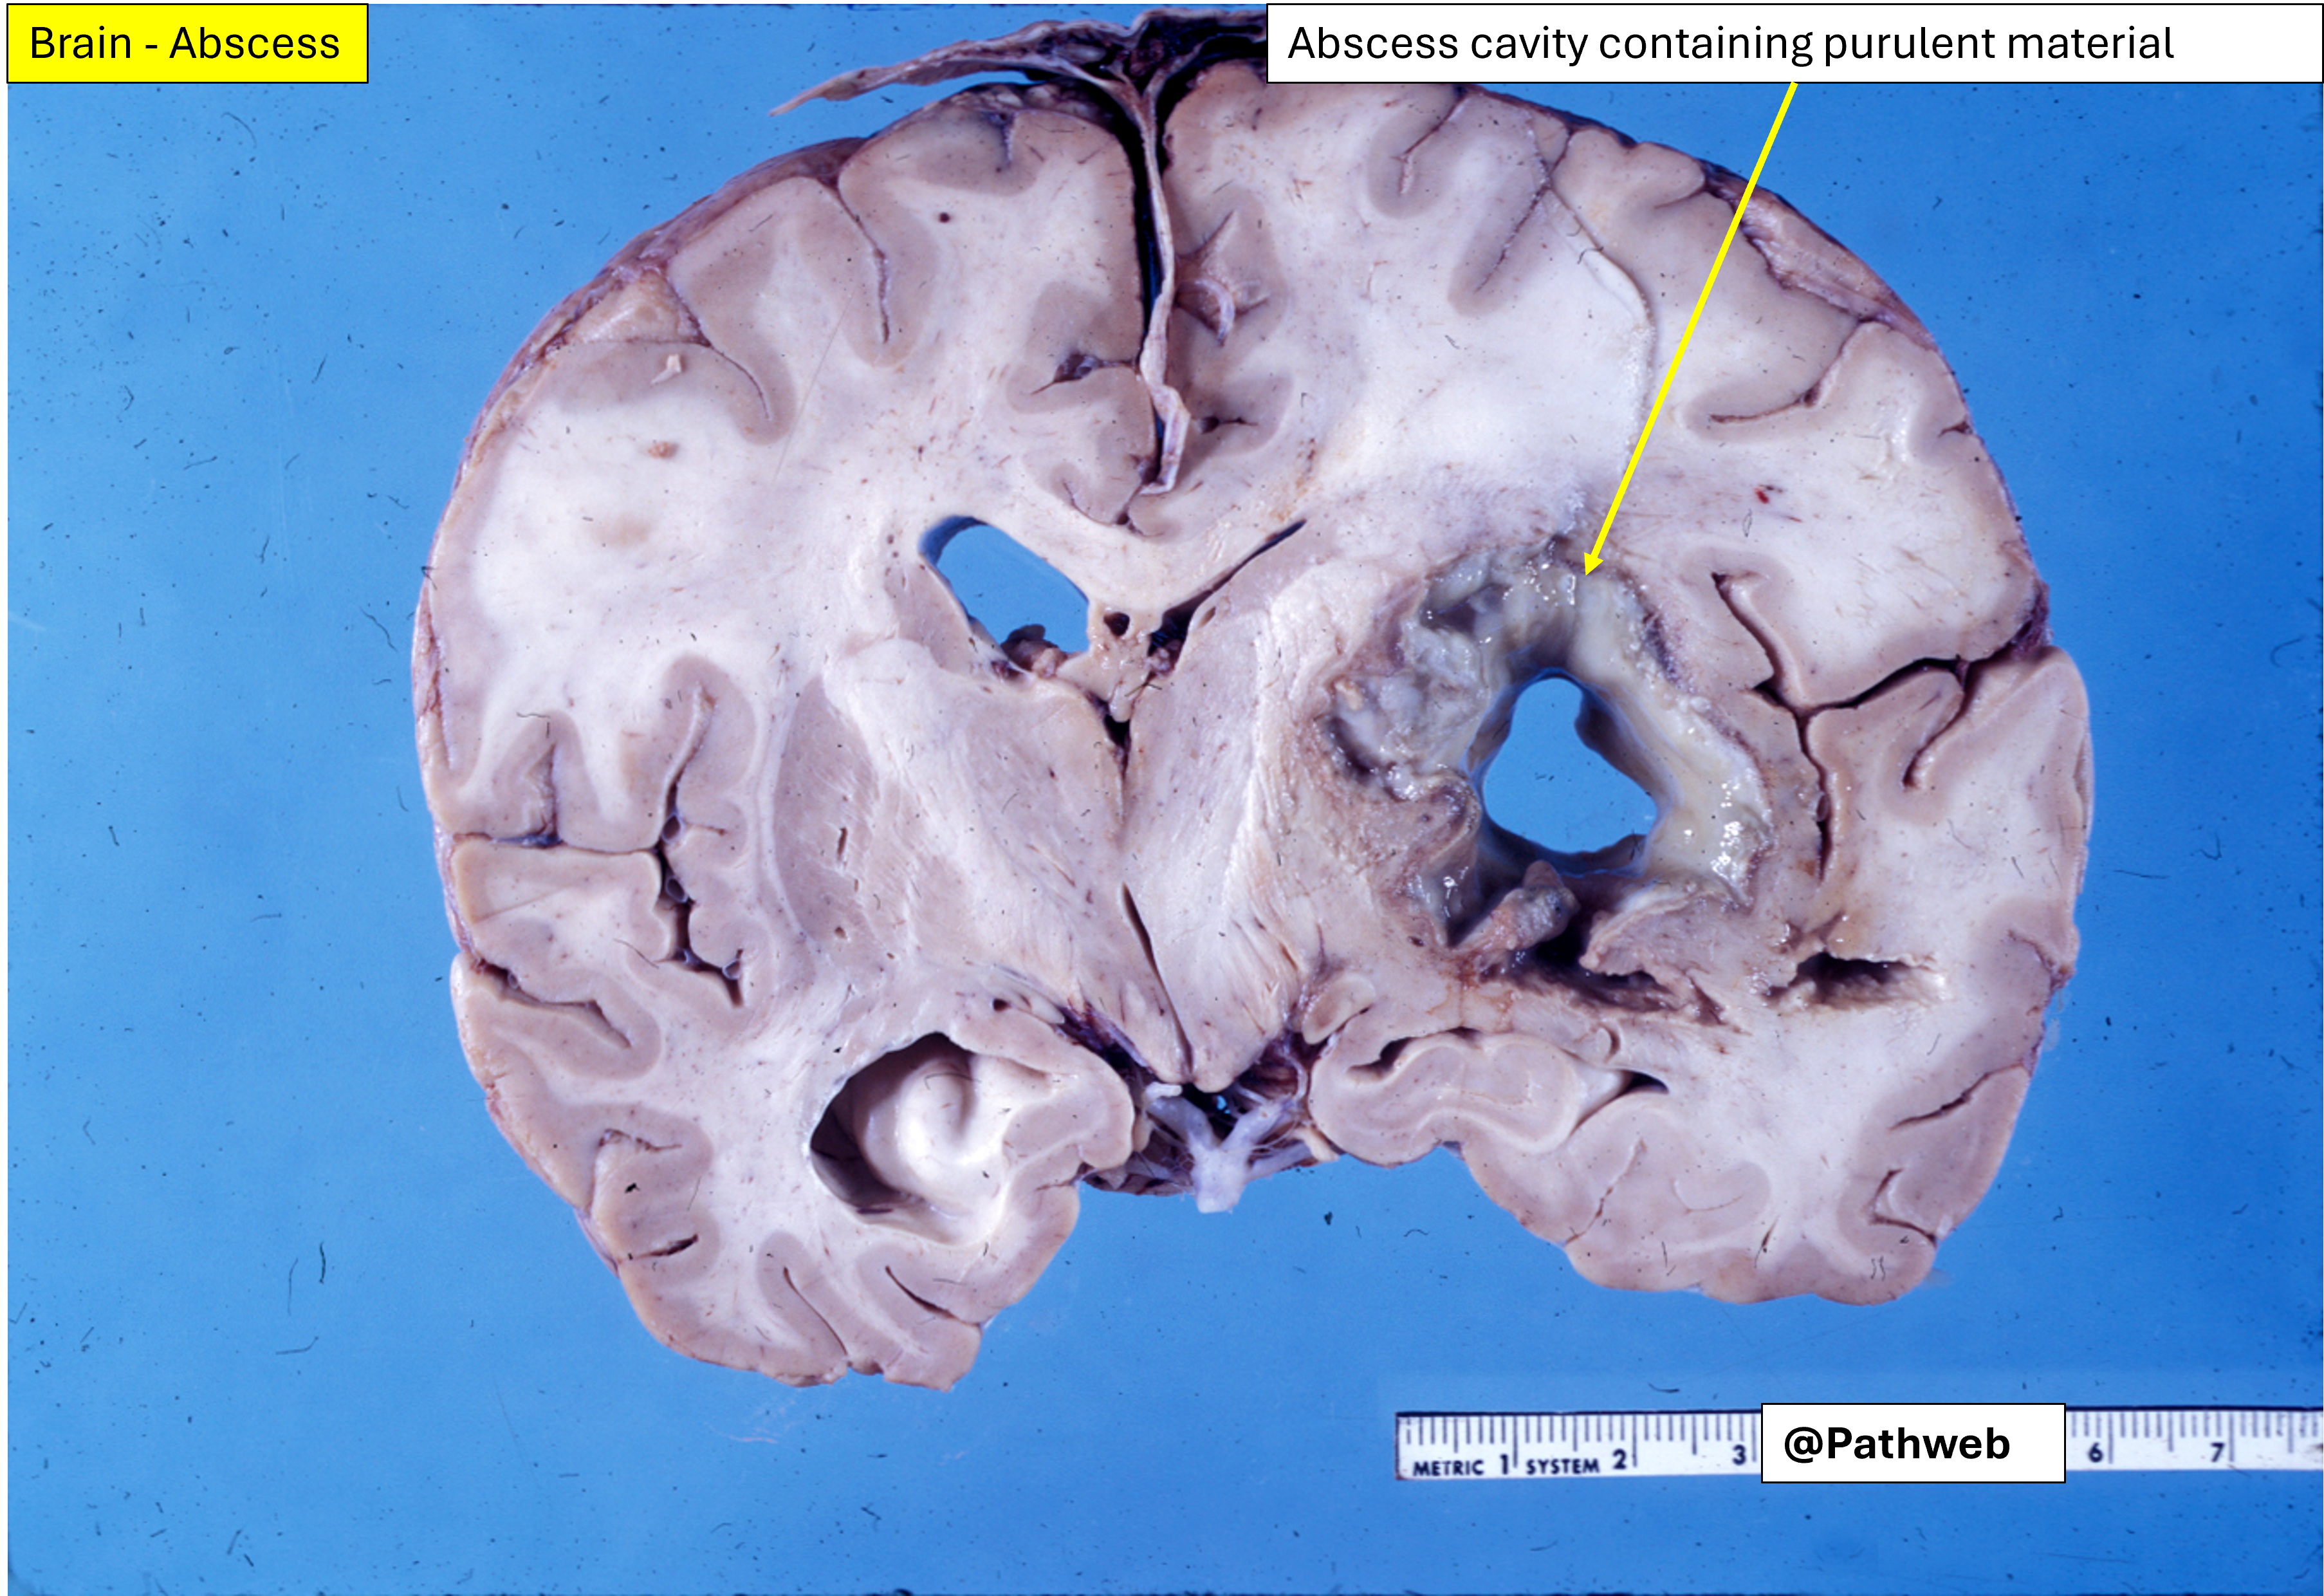

45 year old man with focal neurologic deficits, headache and fever for several weeks.

Cerebrospinal fluid (CSF) analysis showed increase in white cell count, elevated protein concentration but normal glucose content.

The affected cerebral hemisphere is swollen. Cut surface shows a large well-defined cavity (due to liquefactive necrosis and suppuration) lined by a layer of creamy fibrinopurulent exudate resting on a collagenous capsule.

There is compression but no rupture into the lateral ventricle.